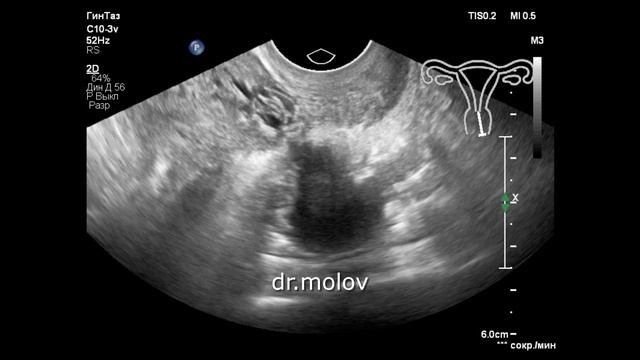

Узи покажет эндометриоз

Узи покажет эндометриоз 110 фото